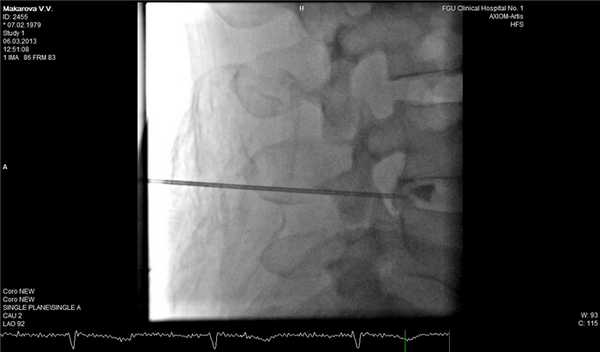

В трудных для диагностики случаях можно дополнительно к МРТ позвоночника применить дискографию, которая достоверно подтвердит или опровергнет диагноз рецидивной грыжи диска. Эпидурография также может быть полезна для оценки состояния корешка в позвоночном канале.

Фораминальная рецидивная грыжа 5 мм. Дискография.

Сдавление корешка L4 в корешковом канале, несмотря на малые размеры грыжи. Эпидурография.